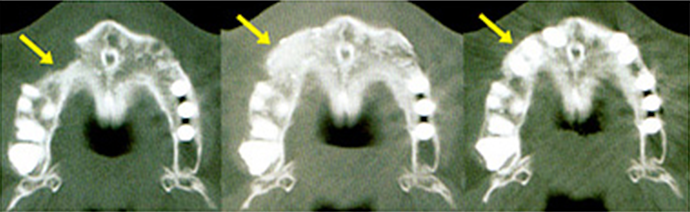

BioNaシミュレーション画像

BioNaシミュレーション画像 歯牙支持型フラップレス

歯牙支持型フラップレス